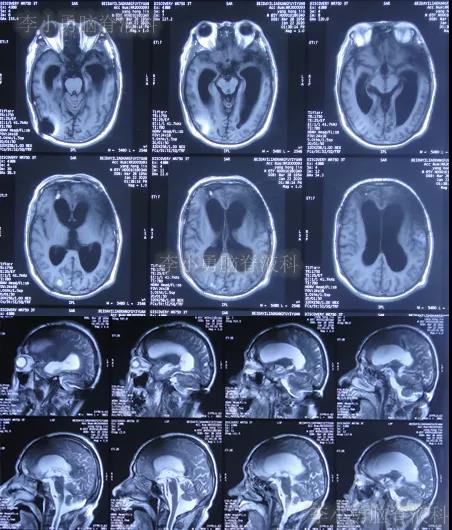

图-11:2019年11月19日腰椎核磁

开颅术后33天即2019年11月21日,查头颅CT(图-12)后认为无明显异常随后出院。

图-12:2019年11月21日头颅CT